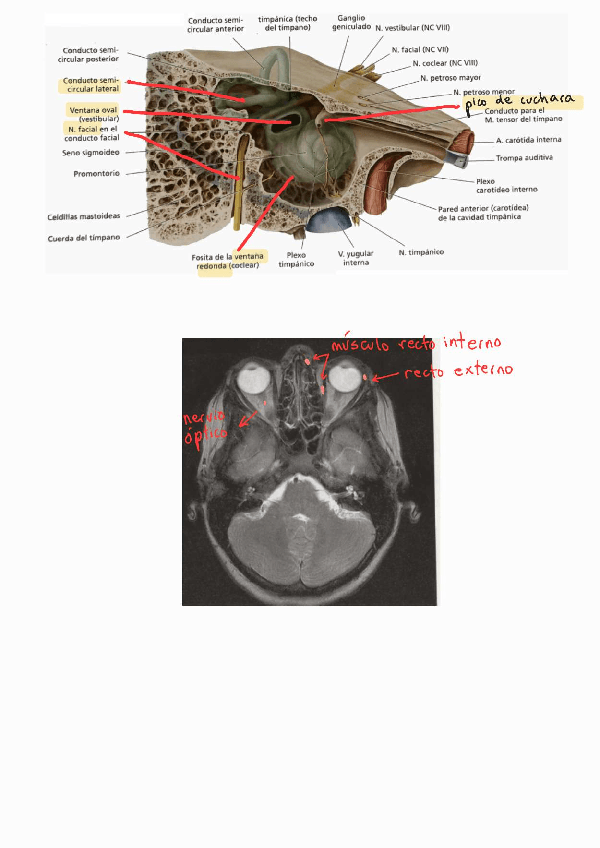

He publicado nuevos apuntes de 2º Anatomía Humana: Estesiología y Sistema Nervioso: RECOPILACIÓN de IMÁGENES de EXÁMENES.pdf

Para la clínica, en esta tabla recogí los síntomas de las lesiones de los pares y sus causas (irrigación, enfermedades o daños) )